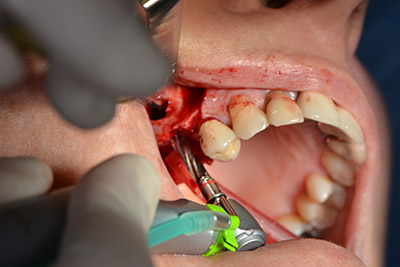

The classic incision (crestal, buccal relief) and the preparation of the mucoperiosteal flap enabled a good overview.

Sky implants (bredent) were used in this case. The surgical protocol of these, specify pilot drilling at about 1200 rpm (Fig. 9).